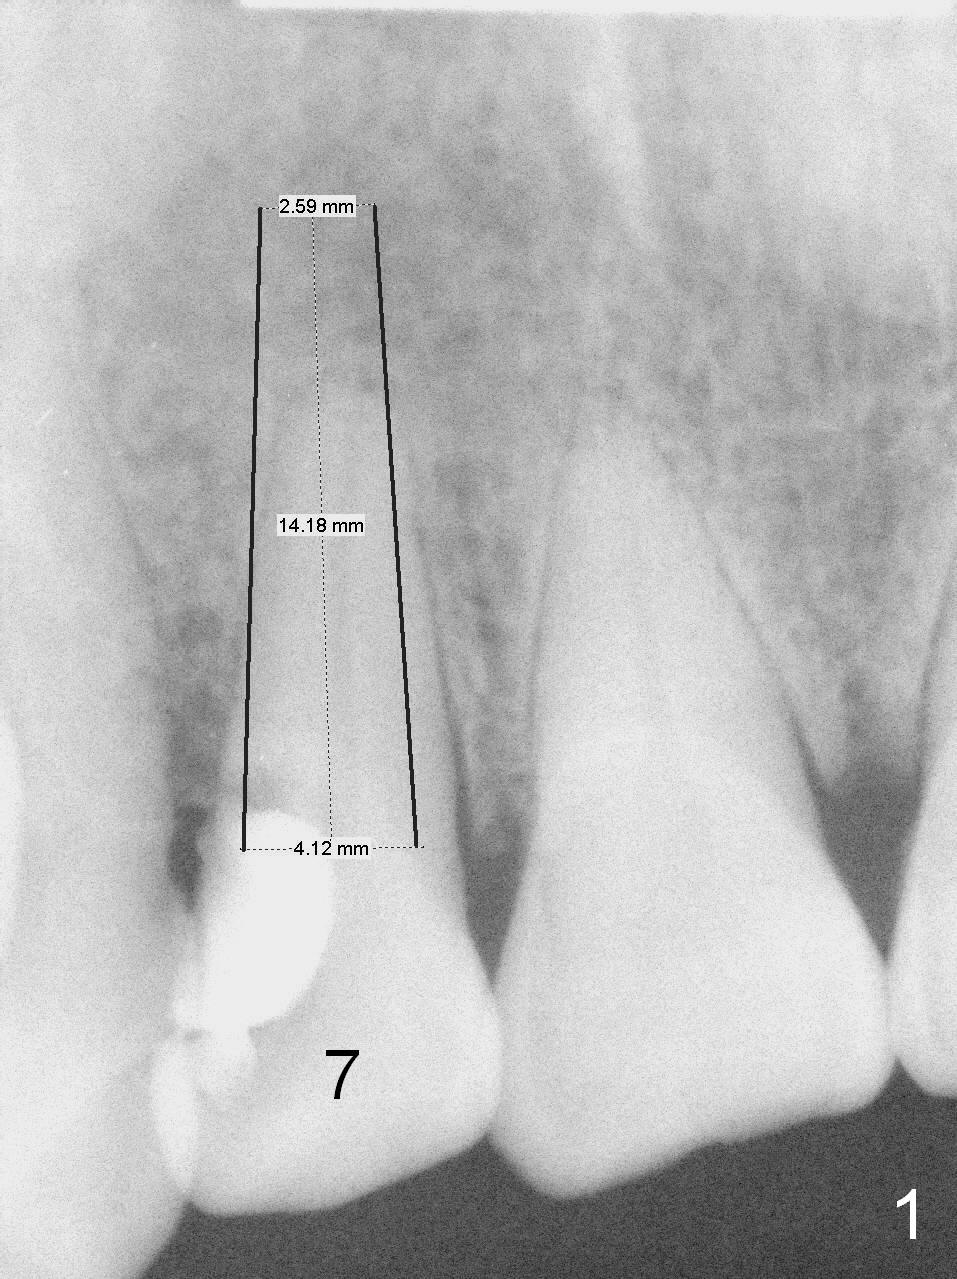

Root Fracture of Lateral Incisor with Possible Buccal Plate Defect

A 52-year-old man had a non-restorable lateral incisor 3 years ago (Fig.1). It fractures lately (Fig.2) with a buccal abscess (Fig.3 *) ) and fistula (>, possible severe buccal plate defect, prepare PRF). Severe deep bite (Fig.4) and malocclusion (Fig.5) will present a challenge to implant provisional restoration.